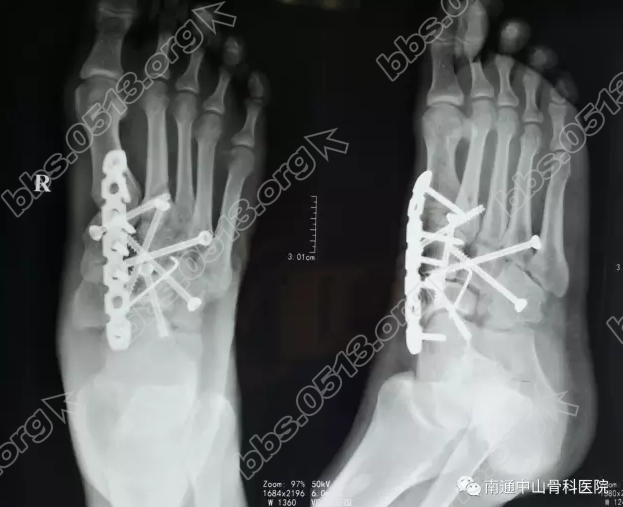

来到我院后立马对小伙进行了检查。通过右足正斜位、CT平扫可以显示,患者为右足楔状骨、骰骨、舟状骨、跖骨骨折;左踝关节x线片显示,左足跟骨骨折。; A' w( |( D: Q

考虑到患者双足肿胀明显,在进行消炎止痛活血消肿的处理同时,决定为他进行手术治疗。征得病人以及家属同意的基础上,于入院第二天实施“右足楔状骨、骰骨、舟状骨、跖骨骨折、左足跟骨骨折切开复位内固定术”。

8 F9 y) L1 I/ u* G/ G  2017年2月10日上午9:30,胡某被推入手术室,李龙付副主任在助手和麻醉师的默契配合下,规范而熟练的进行一步步的操作,手术历时3小时30分钟后顺利结束。